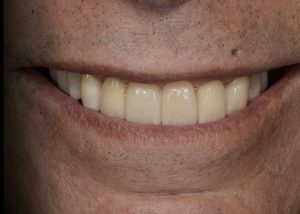

Immediate post-operative view of the inserted provisionals. Fig. 19 (i,ii)